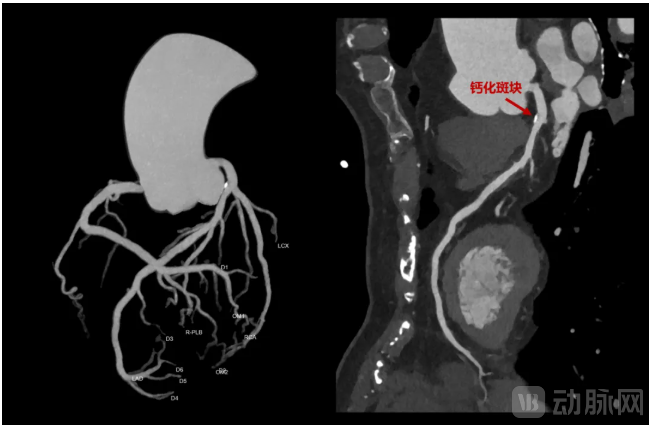

此外,NeuViz 1024还搭载了16cm的超宽探测器。这一应用所呈现的效果是:在心脏成像领域,单圈扫描便可覆盖全心,结合高清画质,既能“冻结”心脏的瞬间跳动,又能清晰呈现冠脉内细微斑块与结构;在胸部扫描时,一次扫描便能进行肺部大范围血管成像时,既能提升患者的舒适性与安全性,又有效提升了肺栓塞等疾病的准确性与诊断效率。

冠脉钙化斑块高清成像